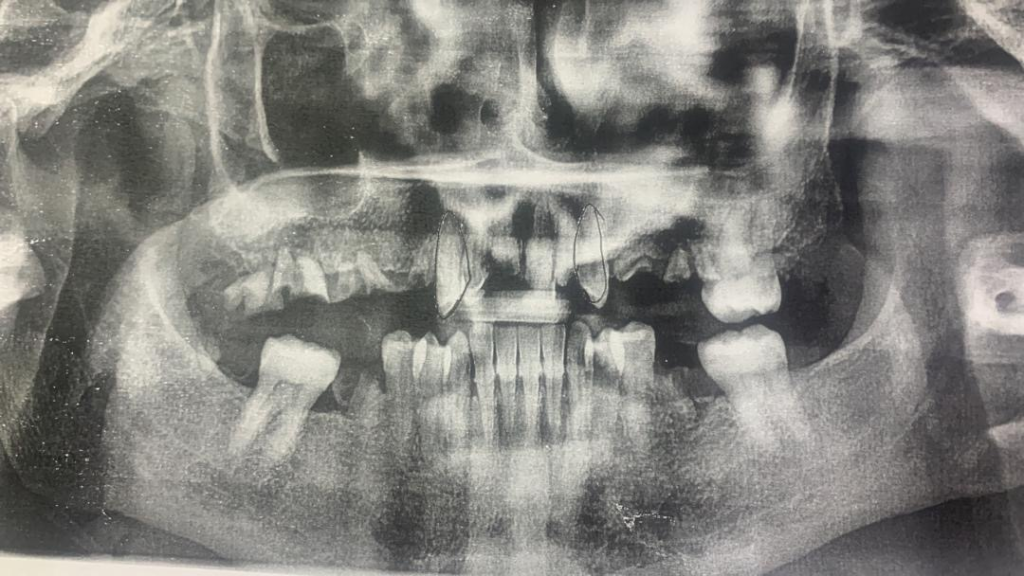

The female patient had been suffering from tooth loss for several years, particularly in the maxillary arch, where almost no functional teeth remained. This condition resulted in compromised masticatory efficiency and impaired speech articulation, the panoramic radiograph was taken before the treatment.

Fig. 2: The panoramic radiograph before treatment